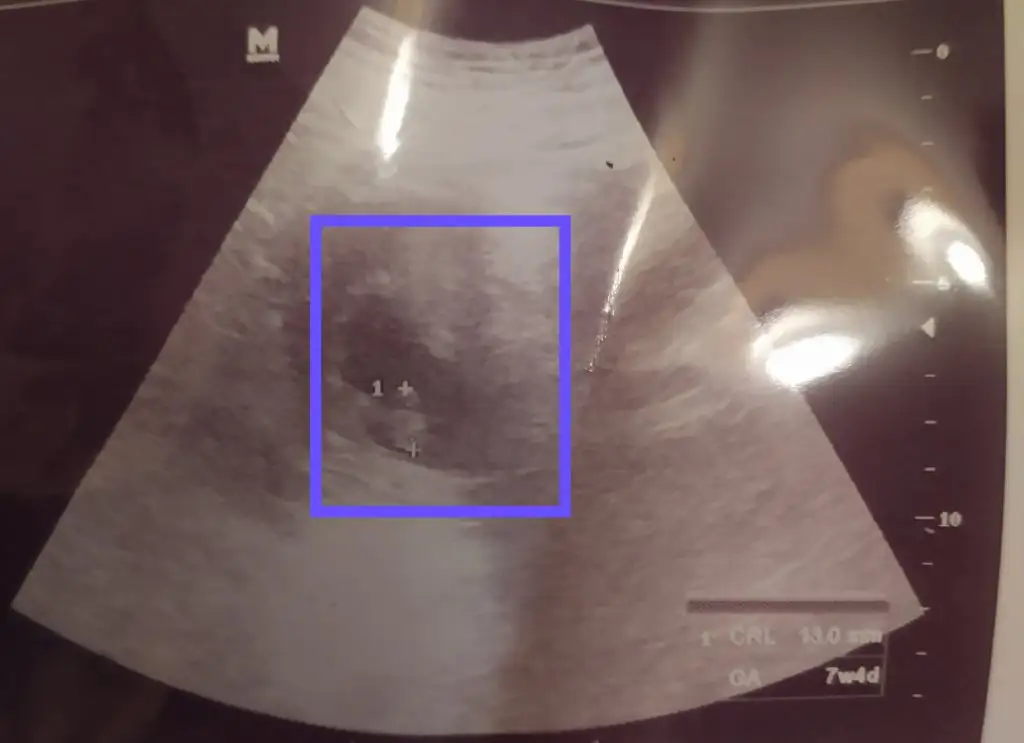

Gözün aydın canımKizlar Selammm, umarım herkes ve bebisleri iyidir. Dün doktor kontrolümüz vardi. 2'li tarama testimiz temiz herşey yolunda görünüyor şuan. Bir dee cinsiyetini öğrendik, Oğlum oluyormuş.

Ben sormuştum canım, bak ekliyorum sana dökümanı. 7. Haftaya göre gayet normal maşallahKalp atışı nasıl yazıyor diye soranlar olmuş benim alttaki şekilde gözüküyordu